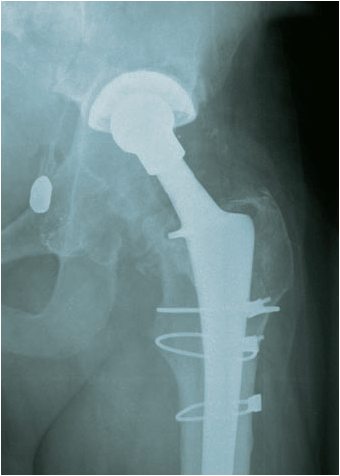

Both hips were examined and pain confirmed on both – and restricted painful movement. It also appeared that the right leg, with the hip replacement was longer than the left leg.

The x-rays confirmed the arthritis in the left hip and this is going to need replacing.

However, it was the right hip, with the Smith & Nephew Birmingham Spectron total hip replacement which caused the most interest:

- Severe oestolysis around the hip – tissue damage.

- Bone erosion (gone totally) for several centimeters below the collar on the inside leg side.

- Damage to the bone on the outside leg side – mottled and insubstantial-looking.

- Signs of movement of the femoral stem of the hip implant – lines down either side and possible bone damage – the cement contains ceramic and this can then act as a grinding past as the stem moves. This has the potential to release more metal ions.

- These signs of movement may explain the feeling of “popping in and out” that I feel – but without dislocation of the hip prosthesis.

Had some new X-rays done today – two months since the last ones – seems to me that there is more osteolysis and bone loss – possibly some fragments but I am not a medical doc and I haven’t discussed these with the surgeon yet. Will do on the day of the surgery.

What is interesting is 3 radio-opaque spots showing up in the pelvic area – not sure what those are.

Quality of the photo’s below – OK for an iPhone 4 shot of the X-Rays held up by my son against a white background!